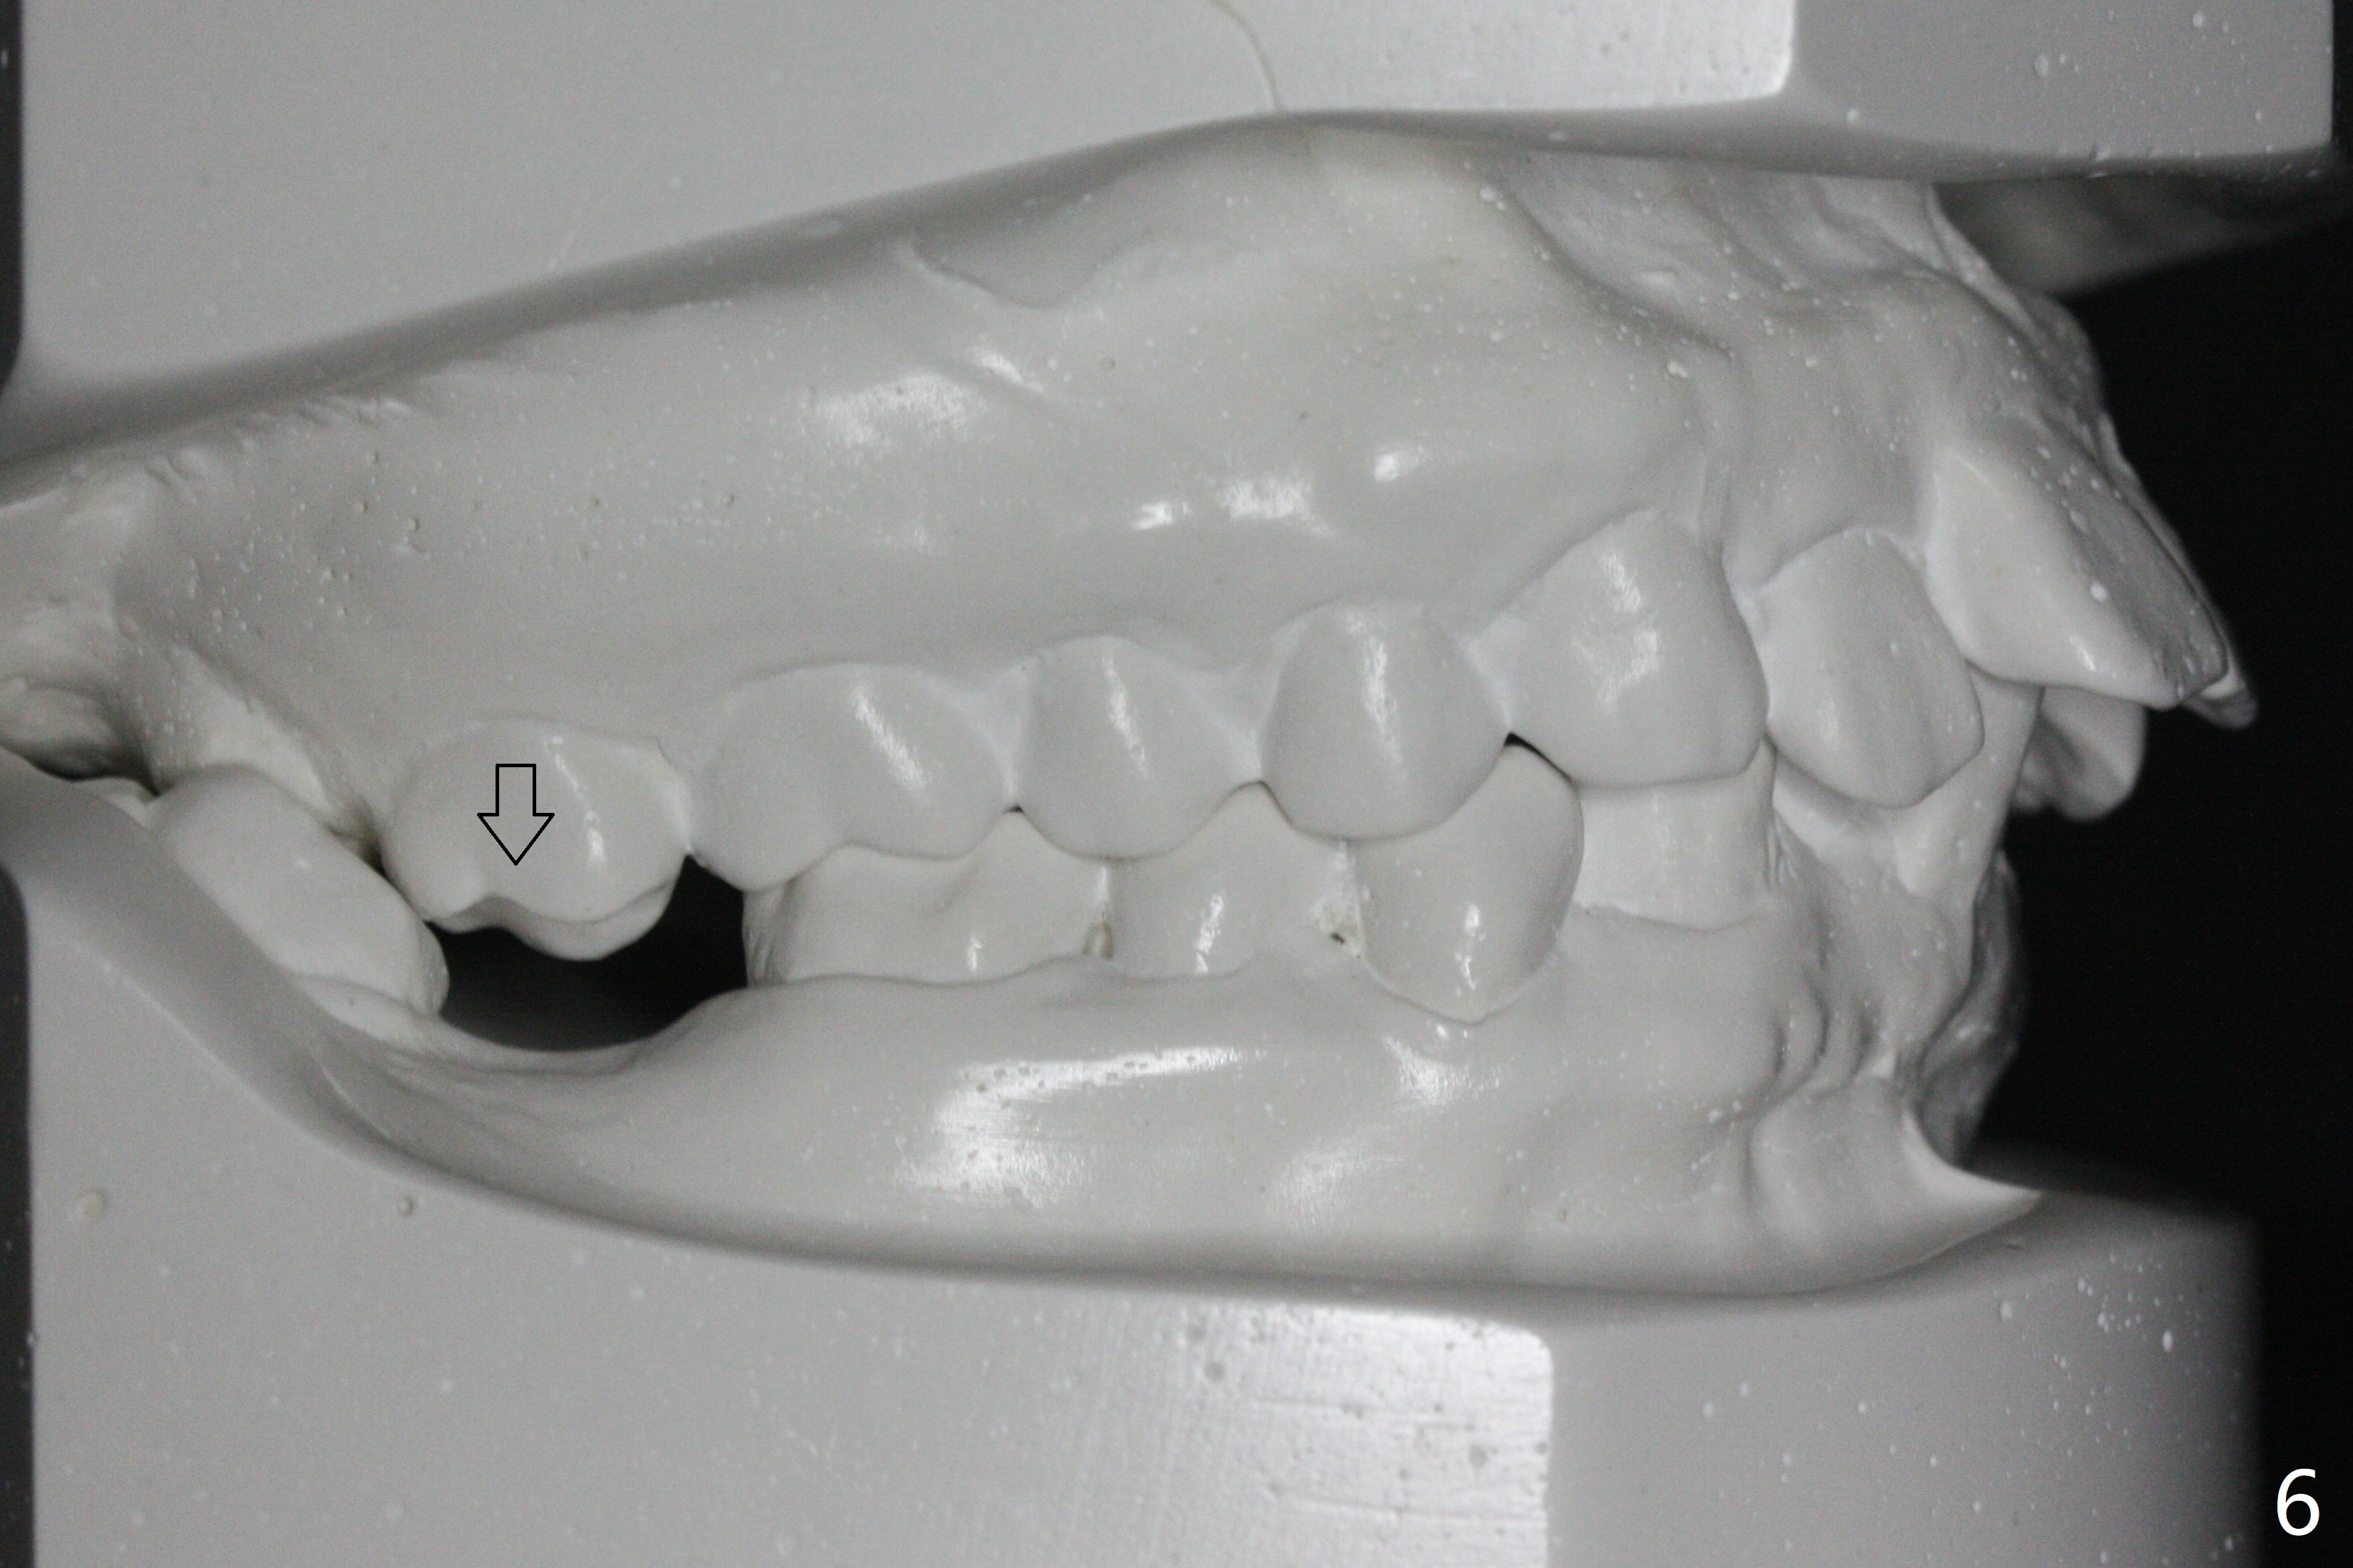

A 41-year-old woman requests ortho, bleach and replacement of 2 lower molars (L7s). The lips are protrusive (Fig.1,3), which is seemingly due to the underlying protrusive anterior teeth (Fig.4,5). Cephalometric tracing shows that SNA and SNB are both 87º (Fig.12), suggesting extraction. When the protrusive teeth are distalized, pay attention to move the upper dental midline to the right (Fig.2). BWs show subgingival calculus. SRP is required. Internal bleaching will be conducted for UL1 (Fig.7,11). Distalization is accomplished with extraction of 2 upper 1st bicuspids and using L8s as anchors so that no implants will be necessary for L7s. But the patient would rather have 2 of the lower 2nd molars for mastication. It appears that extraction of 4 bicuspids is pending (Fig.6-11). Supraeruption of U7s (Fig.6,8 arrows) will be corrected with banding.